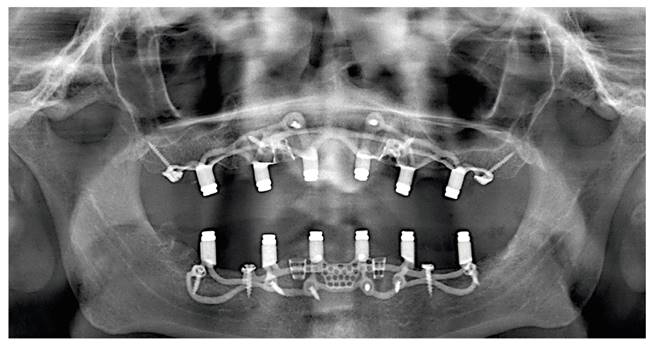

Los implantes subperiósticos o yuxtaóseos son dispositivos médicos utilizados en cirugía maxilofacial y dental para reemplazar dientes perdidos o para estabilizar prótesis dentales.

Estos implantes dentales se colocan debajo del tejido óseo que recubre la mandíbula o el maxilar superior, conocido como periostio, y proporcionan una base sólida y estable para la fijación de los dientes artificiales.

A diferencia de los implantes dentales convencionales que se insertan directamente en el hueso, los implantes subperiósticos se colocan debajo del periostio para aprovechar la mayor cantidad posible de superficie ósea disponible y proporcionar una mayor estabilidad.

En esta fase, el dentista o cirujano maxilofacial evaluará la salud dental y ósea del paciente mediante radiografías y tomografías computarizadas.

Una vez preparado el lugar de colocación del implante dental, se colocará el implante subperióstico debajo del periostio y se asegurará con tornillos especiales.

Con el implante dental totalmente curado, se tomarán impresiones y se fabricará una prótesis dental personalizada para colocar sobre los implantes subperiósticos.

La prótesis dental puede ser una corona individual, un puente fijo o una prótesis dental completa.